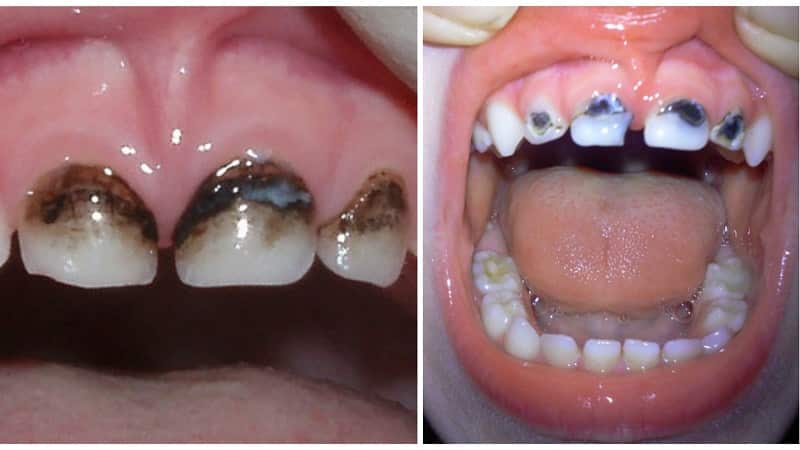

Белые оттенки на зубах ребенка могут иметь желтоватый или коричневатый цвет. Они могут появляться из-за различных факторов, таких как развитие кариеса, недостаточная гигиена полости рта, гипоплазия, употребление кислотной пищи, системные заболевания, травмы зубов, насыщение организма фтором и различные отклонения в развитии ребенка. Гипоплазия может проявляться в виде полос, затемнений или поражений одного или нескольких зубов. Ортодонтическое лечение также может быть причиной поражений, когда скобы предотвращают контакт зубной части с слюной, что препятствует минерализации. Важно обратиться к стоматологу, чтобы установить причину и своевременно устранить проблему. Молочные зубы с белыми пятнами также следует сохранить до появления постоянных зубов. Диагноз может быть сложным, но опытный стоматолог может определить время протекания патологии и факторы раздражения. Также важно уделить внимание иммунной системе ребенка. Появление белых пятен после инфекционных заболеваний, перенесенных зимой, наблюдается у многих детей. Поэтому рекомендуется проводить закаливающие процедуры, заниматься спортом и проводить время на свежем воздухе. Стоматолог учитывает информацию о болезнях матери во время беременности при диагностировании белых пятен на молочных зубах ребенка.

Когда пятна на зубах вызваны кариесом, их можно лечить. Стоматологи удаляют пораженные участки и проводят микропломбирование с использованием специального лака. В случае молочных зубов, не проводится пломбирование, а используется процедура серебрения или покрытие лаком.